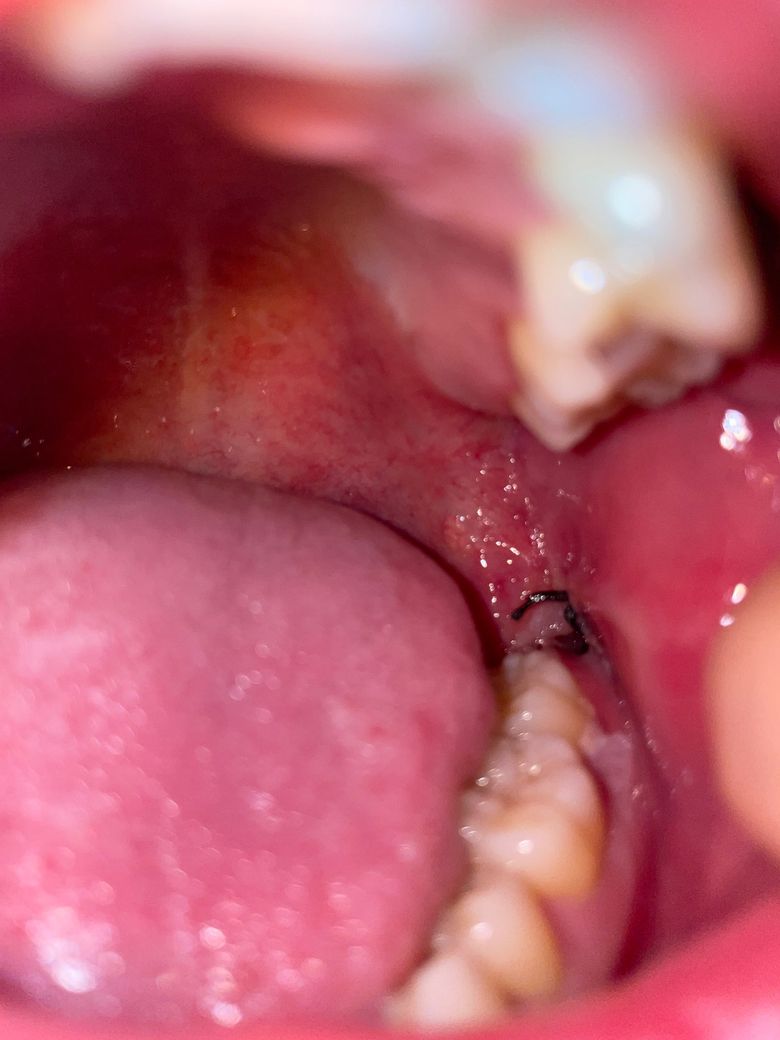

발치와 주변에 회색 ,이거 드라이 소켓인가요?

실밥 주변에 회색이 있어요 금연 금주 하고 있고요

드라이 소켓은 감염의 일종으로 냄새도 많이 나고 통증이 극심합니다. 사진상으로는 크게 문제가 잇어 보이진 않습니다.

드라이소켓이 생기게 되면 보통 해당 부위에 극심한 통증이 느껴지고 냄새가 나게 됩니다. 특별한 냄새가 나지 않고 통증이 없다면 드라이소켓 가능성은 낮습니다.

지금 발치 3일 차인데 통증이나 붓기가 조금 있어서 냉찜질 연장해서 하고 있어요 그리고 볼안쪽이 간지럽거나 어금니가 시린경우는 뭔가요? -> 드라이소켓 양상은 아닙니다. 발치 후 주의사항 앞으로도 잘 지키시면 됩니다